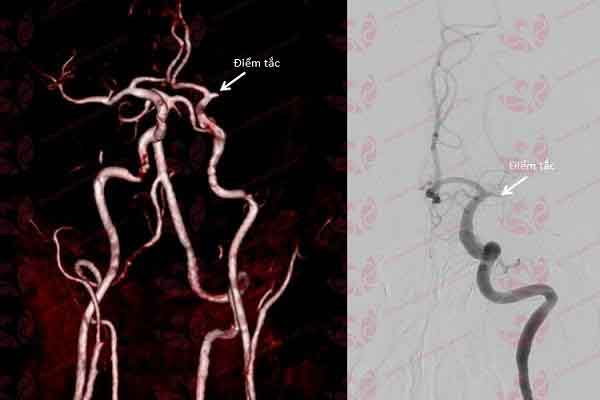

Nhờ ứng dụng phần mềm trí tuệ nhân tạo Rapid, các bác sĩ đã xác định tổn thương nhanh nhất và đưa ra phương pháp điều trị chính xác kịp thời – Ảnh: BVCC

Tại đây, các bác sĩ đã ứng dụng phần mềm trí tuệ nhân tạo Rapid xử lý, đánh giá và phân tích hình ảnh tự động về tình trạng bệnh nhân. Nhờ ứng dụng trí tuệ nhân tạo Rapid này đã giúp các bác sĩ đưa ra quyết định cực kỳ nhanh chóng để can thiệp lấy huyết khối động mạch não do tắc hoàn toàn động mạch não trái.

Bệnh nhân đã được can thiệp lấy huyết khối ở động mạch não kịp thời – Ảnh: BVCC